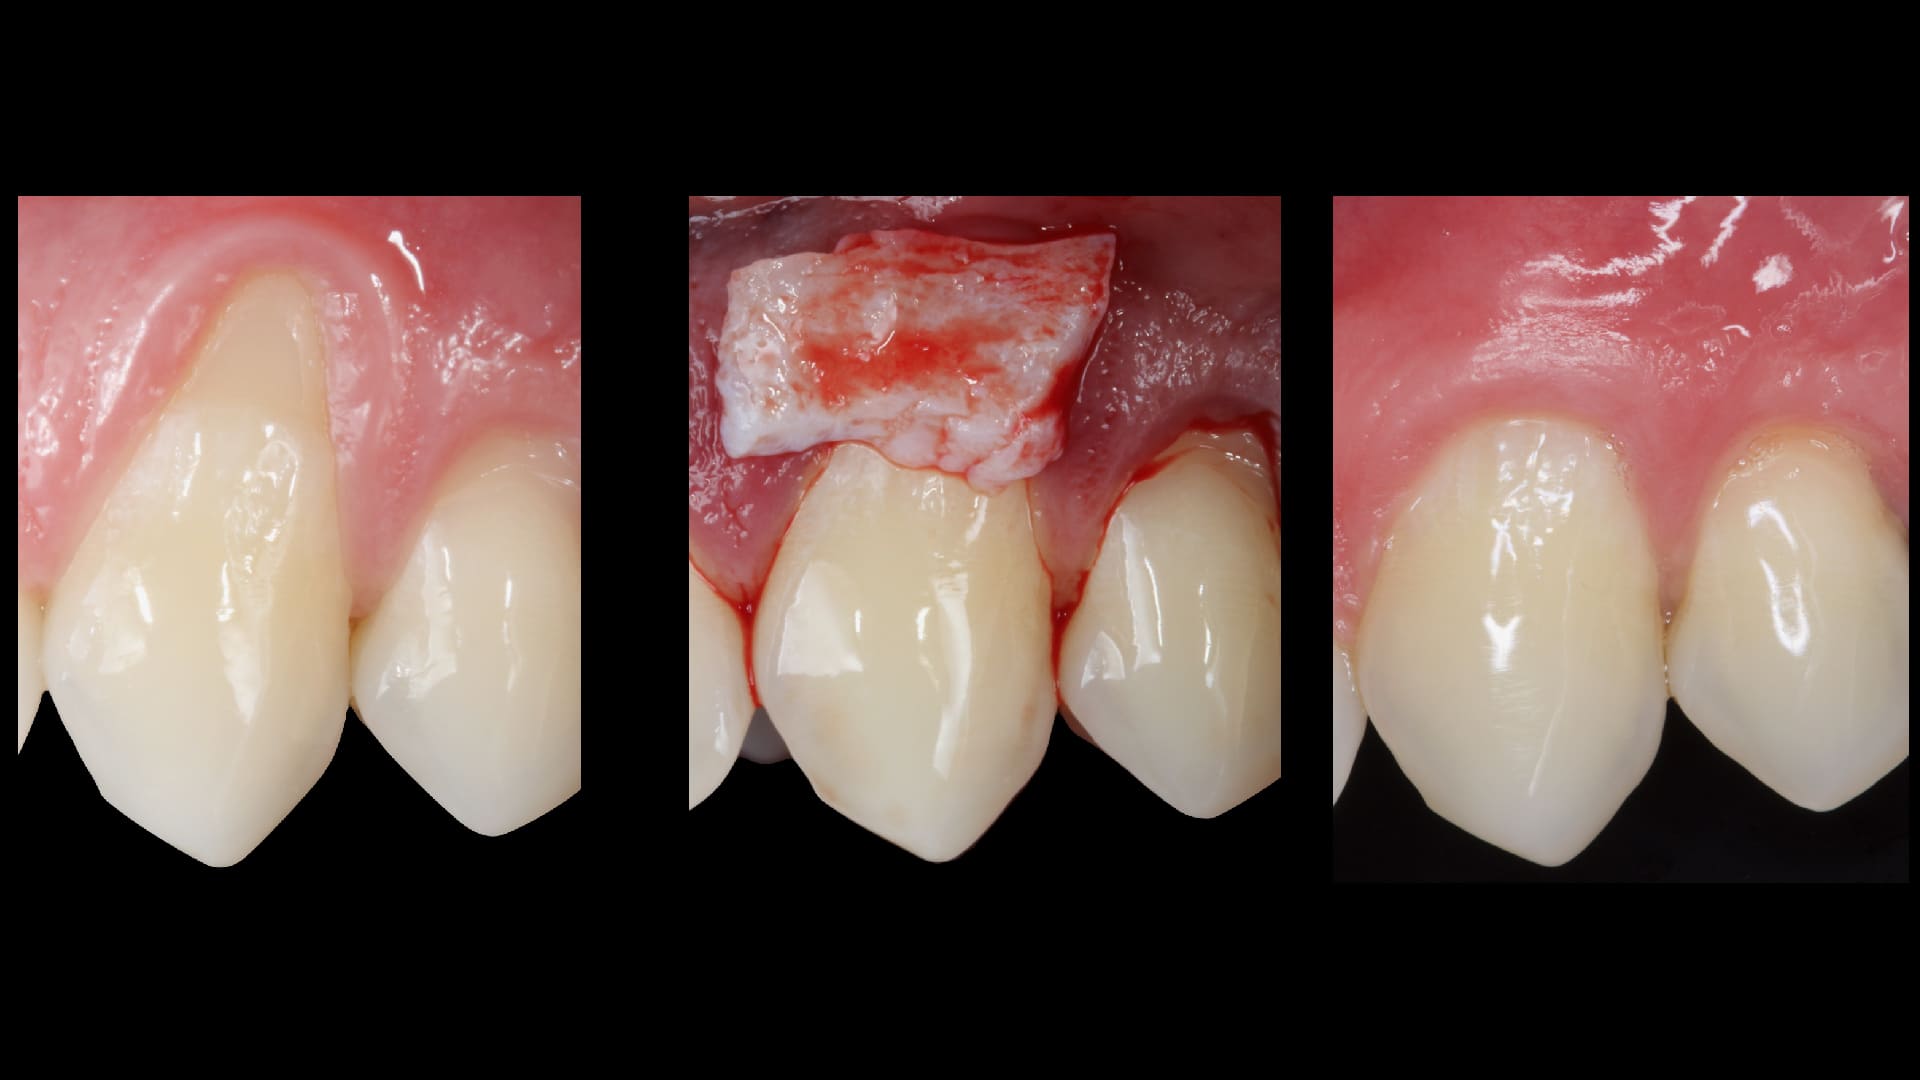

Root Coverage procedures.

Socket reconstruction with biomaterials and CTG

Soft tissue grafting and harvesting techniques.